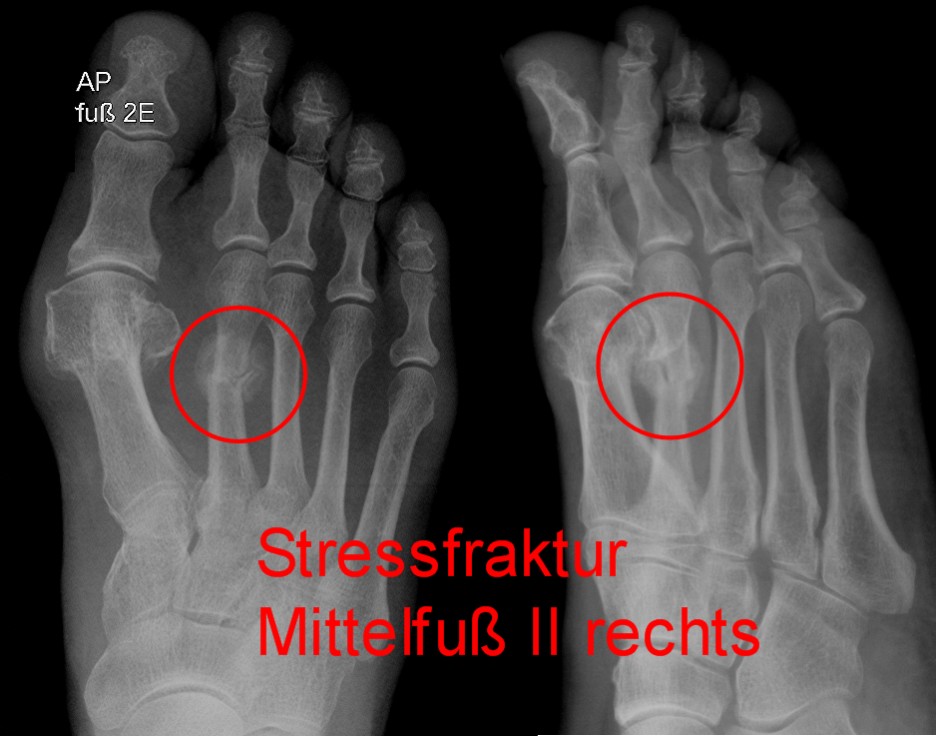

Stressfraktur (Marschfraktur): Fehl- und Überlastung

Im Röntgenbild ist am 2. Strahl der Mittelfußknochen ein Ermüdungsbruch (roter Kreis) sichtbar. © Gelenk-Klinik

Häufig treten Fußschmerzen nach langanhaltenden Belastungen beim Wandern oder Joggen auf: Bei der Stressfraktur erfolgt ein Ermüdungsbruch im Fuß aufgrund der immer wiederkehrenden Dauerbelastung der Knochen. Meist sind die Mittelfußknochen betroffen. Diese Stress- oder Marschfraktur ist von Schwellungen und stechenden Schmerzen beim Auftreten begleitet. Die Symptome treten meist plötzlich von einem Augenblick auf den nächsten auf.